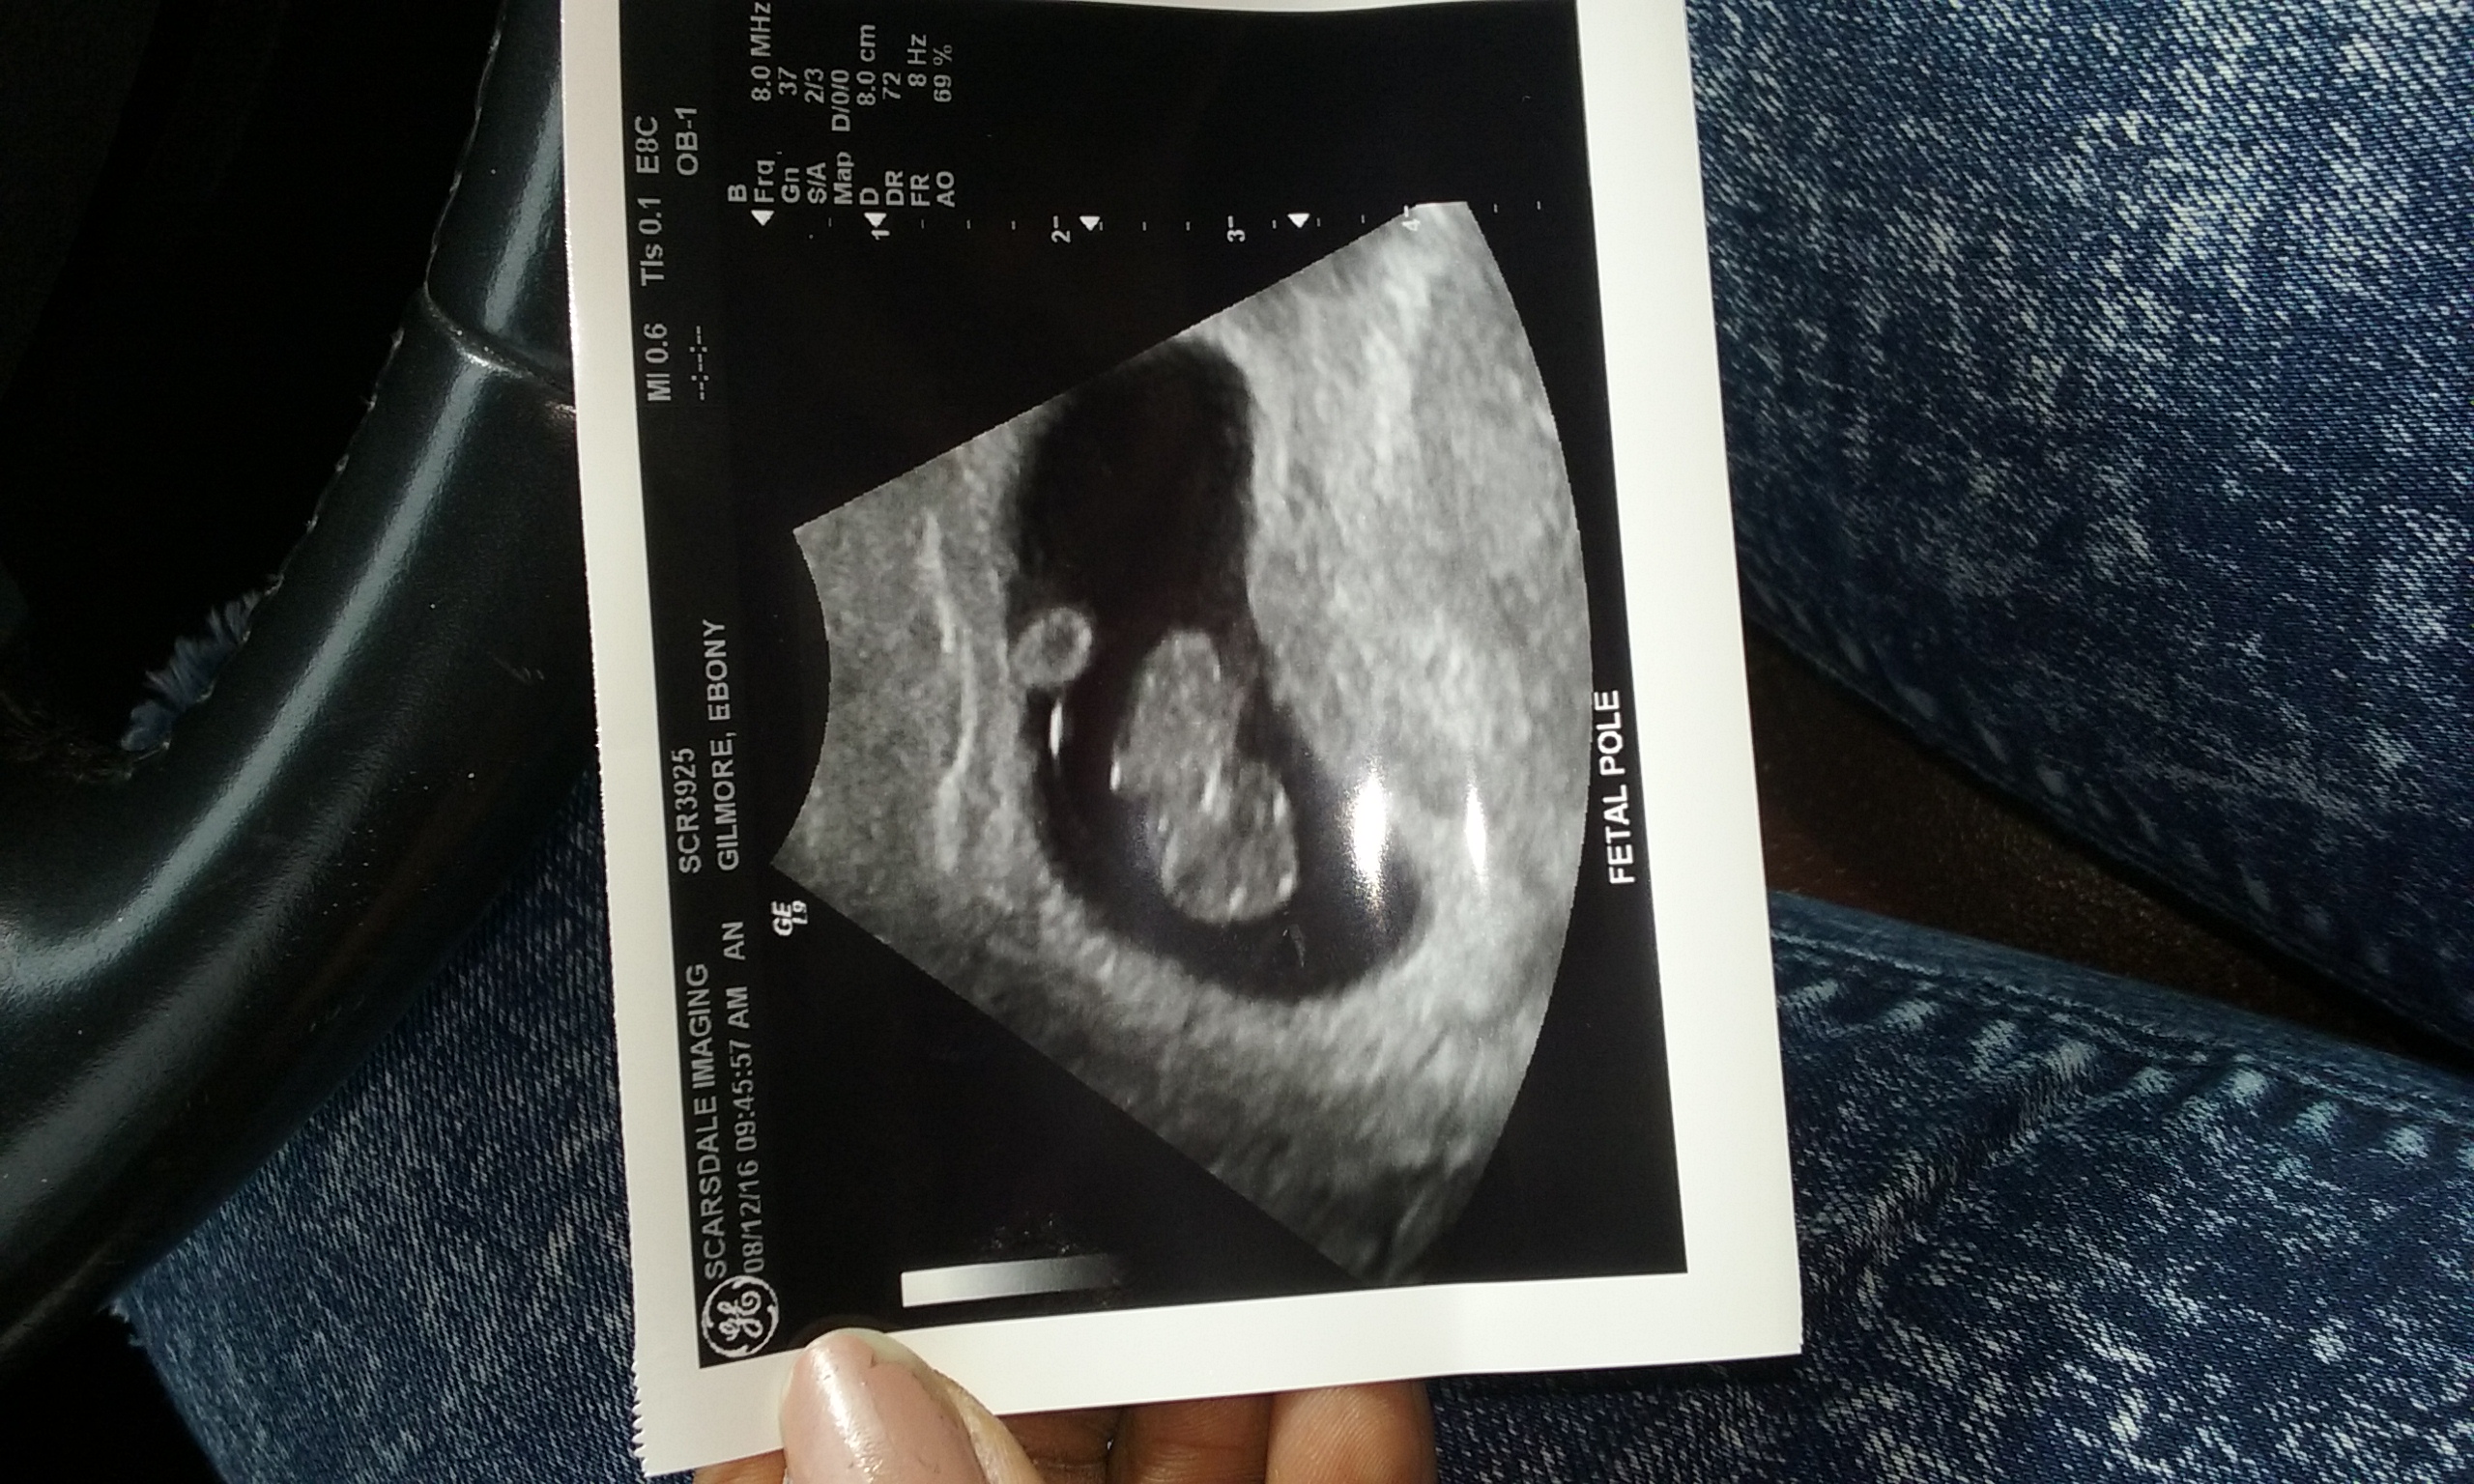

7week 6day transvaginal.. Any guesses?Attachment 33066

http://uploads.tapatalk-cdn.com/2016...8f1d3aeccb.jpg so I just got my ultrasound back from the gender expert and supposedly they said because the placenta is on the left I'm more likely to have a girl but that's yet to be seen so I'm still doubtful about it about this theory and all.

I say BOY!